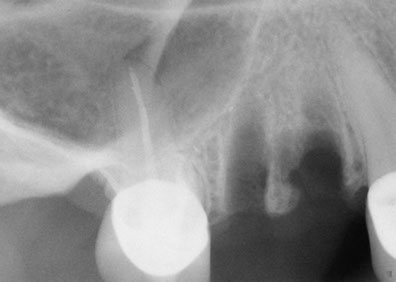

Una solución rápida y segura para hacer posible la instalación de implantes dentalesFue Philip Boyne, quien en 1960 utilizo por primera vez la técnica Caldwell-Luc, empleada para corregir la falta de espacio maxilo-mandibular elevando la Membrana Sinusal en la zona de molares y premolares, colocando en la base del seno un injerto compuesto por hueso particulado o corticoesponjoso autógeno (que se origina o engendra a sí mismo ) para el relleno de esta cavidad ósea, con la llegada de los implantes de titanio radiculares, se observó que muchas zonas maxilares posteriores, eran inadecuadas en altura y anchura ósea, por lo que se requirió injertar hueso dentro del seno maxilar para hacerlas adecuadas receptoras de implantes. La elevación de senos, es una técnica quirúrgica necesaria cuando no hay suficiente hueso, se añade hueso entre el maxilar superior y los senos maxilares, que son un anexo de las fosas nasales por lo que están en ambos lados de la nariz, la forma y el tamaño de este seno varían en cada persona y con el paso de los años se va haciendo más grande (inadecuado para implantes dentales).

Esta técnica es empleada en cirugía dento-alveolar, oncología y traumatología, con el objeto de dar arreglo a un defecto óseo craneofacial etc. La elevación de seno es una solución segura a través de la cual es posible la instalación de los implantes dentales osteointegrados, dando como resultado estética y funcionalidad a la dentadura, este procedimiento es también conocido como Sinus Lift.

¿Para quién esta indicada esta técnica?Esta técnica esta recomendada en aquellos casos donde es imposible colocar implantes dentales con la longitud óptima en la parte posterior del maxilar superior ya que en esta región se posee generalmente una calidad ósea Tipo III ó IV y por esto es necesario utilizar implantes de una longitud mínima de 10mm y del mayor diámetro posible.